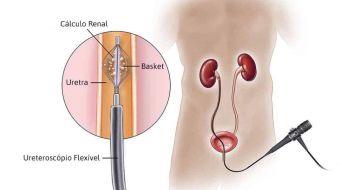

Ureteroscopia

Um fino aparelho endoscópico (ureteroscópio) semirrígido ou flexível é introduzido na via urinária em direção ao cálculo que, assim que identificado, é fragmentado com litotritor a laser, em seguida retirado com pinças. Geralmente, após o procedimento, é necessária a colocação de um cateter chamado duplo jota, que faz a drenagem urinária e de fragmentos.